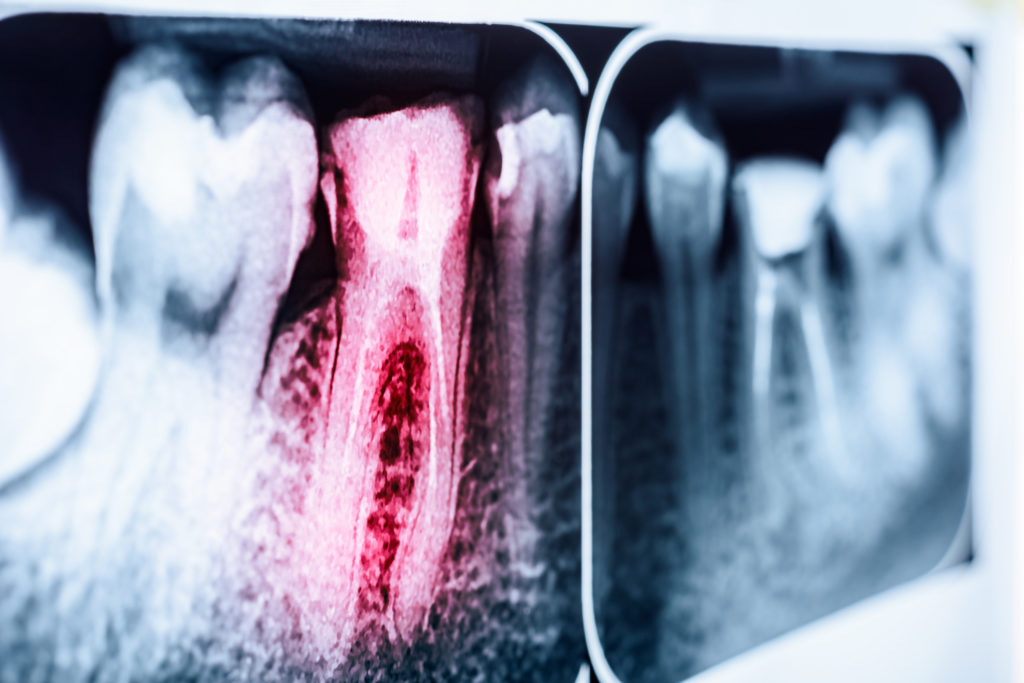

The two launched a clinical study to test the theory which was eventually published in the British Medical Journal. Of the children in the group, all showed fully erupted or badly formed teeth with dental caries (cavities). They recorded the degree of hardness of the children’s teeth as well as other qualities they would measure after changing their diets.

By strictly controlling the children’s diets, much to their chagrin, they transitioned them from cereal-rich, to vitamin D and calcium-rich foods for a period of six months. They found that there was an arrest in the development of new and existing caries and even found in some cases a re-mineralization of teeth.

They also saw that on average, there were 4.7 teeth per child that showed signs of arrest in existing caries. Their study noticed that oatmeal was a specific contributor in the cereal category, which was a major staple of the children’s diets. Mellanby and her colleague conceded that their study was done on bed-ridden children who were not active, making it easier to feed them a carbohydrate-restricted diet. They said that for healthy children, completely cutting out carbs wasn’t necessary, but restricting them could have a significant impact on healthy teeth.